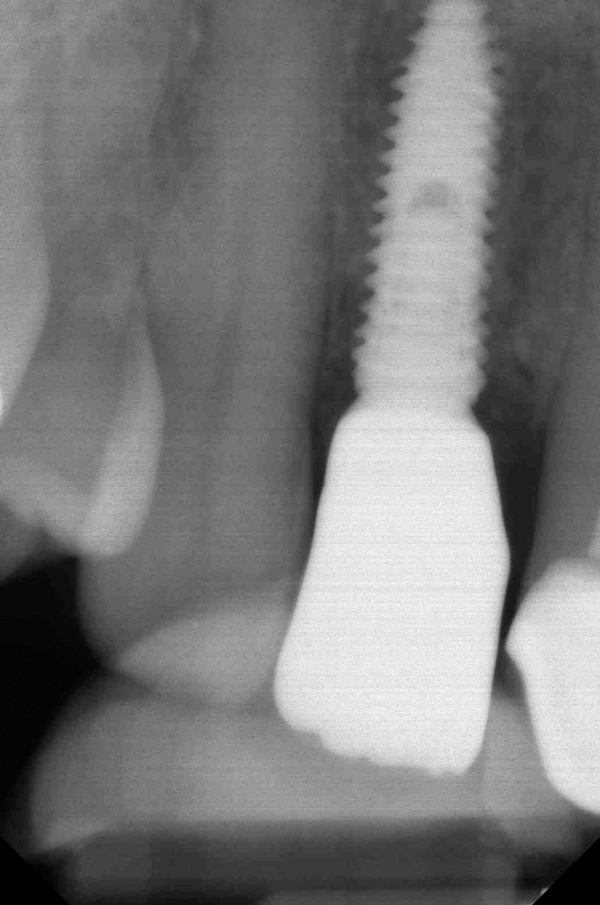

Fig 4. Radiograph showing root fracture and apical lesion of the tooth (No. 7).

Figure 4

To predict peri-implant esthetic outcomes, Kois described five essential diagnostic keys that need to be assessed before removing a periodontally hopeless tooth (Figure 3 and Figure 4): (1) relative tooth position; (2) form of the periodontium; (3) periodontal biotype; (4) tooth shape; and (5) position of the osseous crest. Failing teeth that have a thick, flat gingival biotype, are square shaped, and have < 3 mm vertical distance from the position of the facial and interproximal crest have the lowest risk of developing recessions after implant placement.23 Therefore, implant surgery may be performed by either an open flap or flapless approach. However, teeth with a thin soft-tissue biotype, a highly scalloped gingival architecture, and a triangular shape that are positioned facially have less-predictable peri-implant esthetic outcomes. When a tooth presents with these unfavorable anatomical features, grafting procedures should be considered both before and after tooth extraction to prevent vertical loss and facial collapse of the gingival architecture.21 Flapless tooth extraction should be attempted in the esthetic zone to maintain blood supply from the periosteum and endosteum and maximize healing potential (Figure 5).44 In addition, several surgical protocols have been proposed to avoid peri-implant mucosal recessions, including 3-dimensional implant positioning,45,46 the use of platform-switching implants,47,48 and soft-tissue augmentation.8,49,50

When placing an implant in the esthetic zone, ideal 3-dimensional positioning, including mesio-distal, apico-coronal, and orofacial dimensions, is essential to achieve favorable esthetic outcomes, regardless of the implant system used (Figure 6).45 With respect to the orofacial dimension, implants should be placed in a more palatal or lingual position to allow the presence of at least 2 mm of buccal bone thickness from the implant buccal shoulder.45,46 When the distance of the buccal bone wall and implant buccal shoulder is < 2 mm, a significantly higher incidence of midfacial recession has been previously reported.3,12 Placement of bone graft (Figure 7) and immediate restoration (Figure 8 and Figure 9) at the time of implant placement has also been suggested to increase peri-implant soft-tissue height and thickness.51 In the apico-coronal dimension, the implant head should be at least 3 mm apical to an imaginary line connecting the CEJ of the adjacent teeth and 1 mm to 2 mm apical to the interproximal and crestal bone to ensure a proper implant emergence profile and facilitate proper implant restoration (Figure 10). Regarding the horizontal implant–tooth distance, implants should be placed no closer than 1.5 mm from the adjacent root surface to minimize resorption of the interproximal alveolar crest, which causes a reduction in the papillary height.46,52